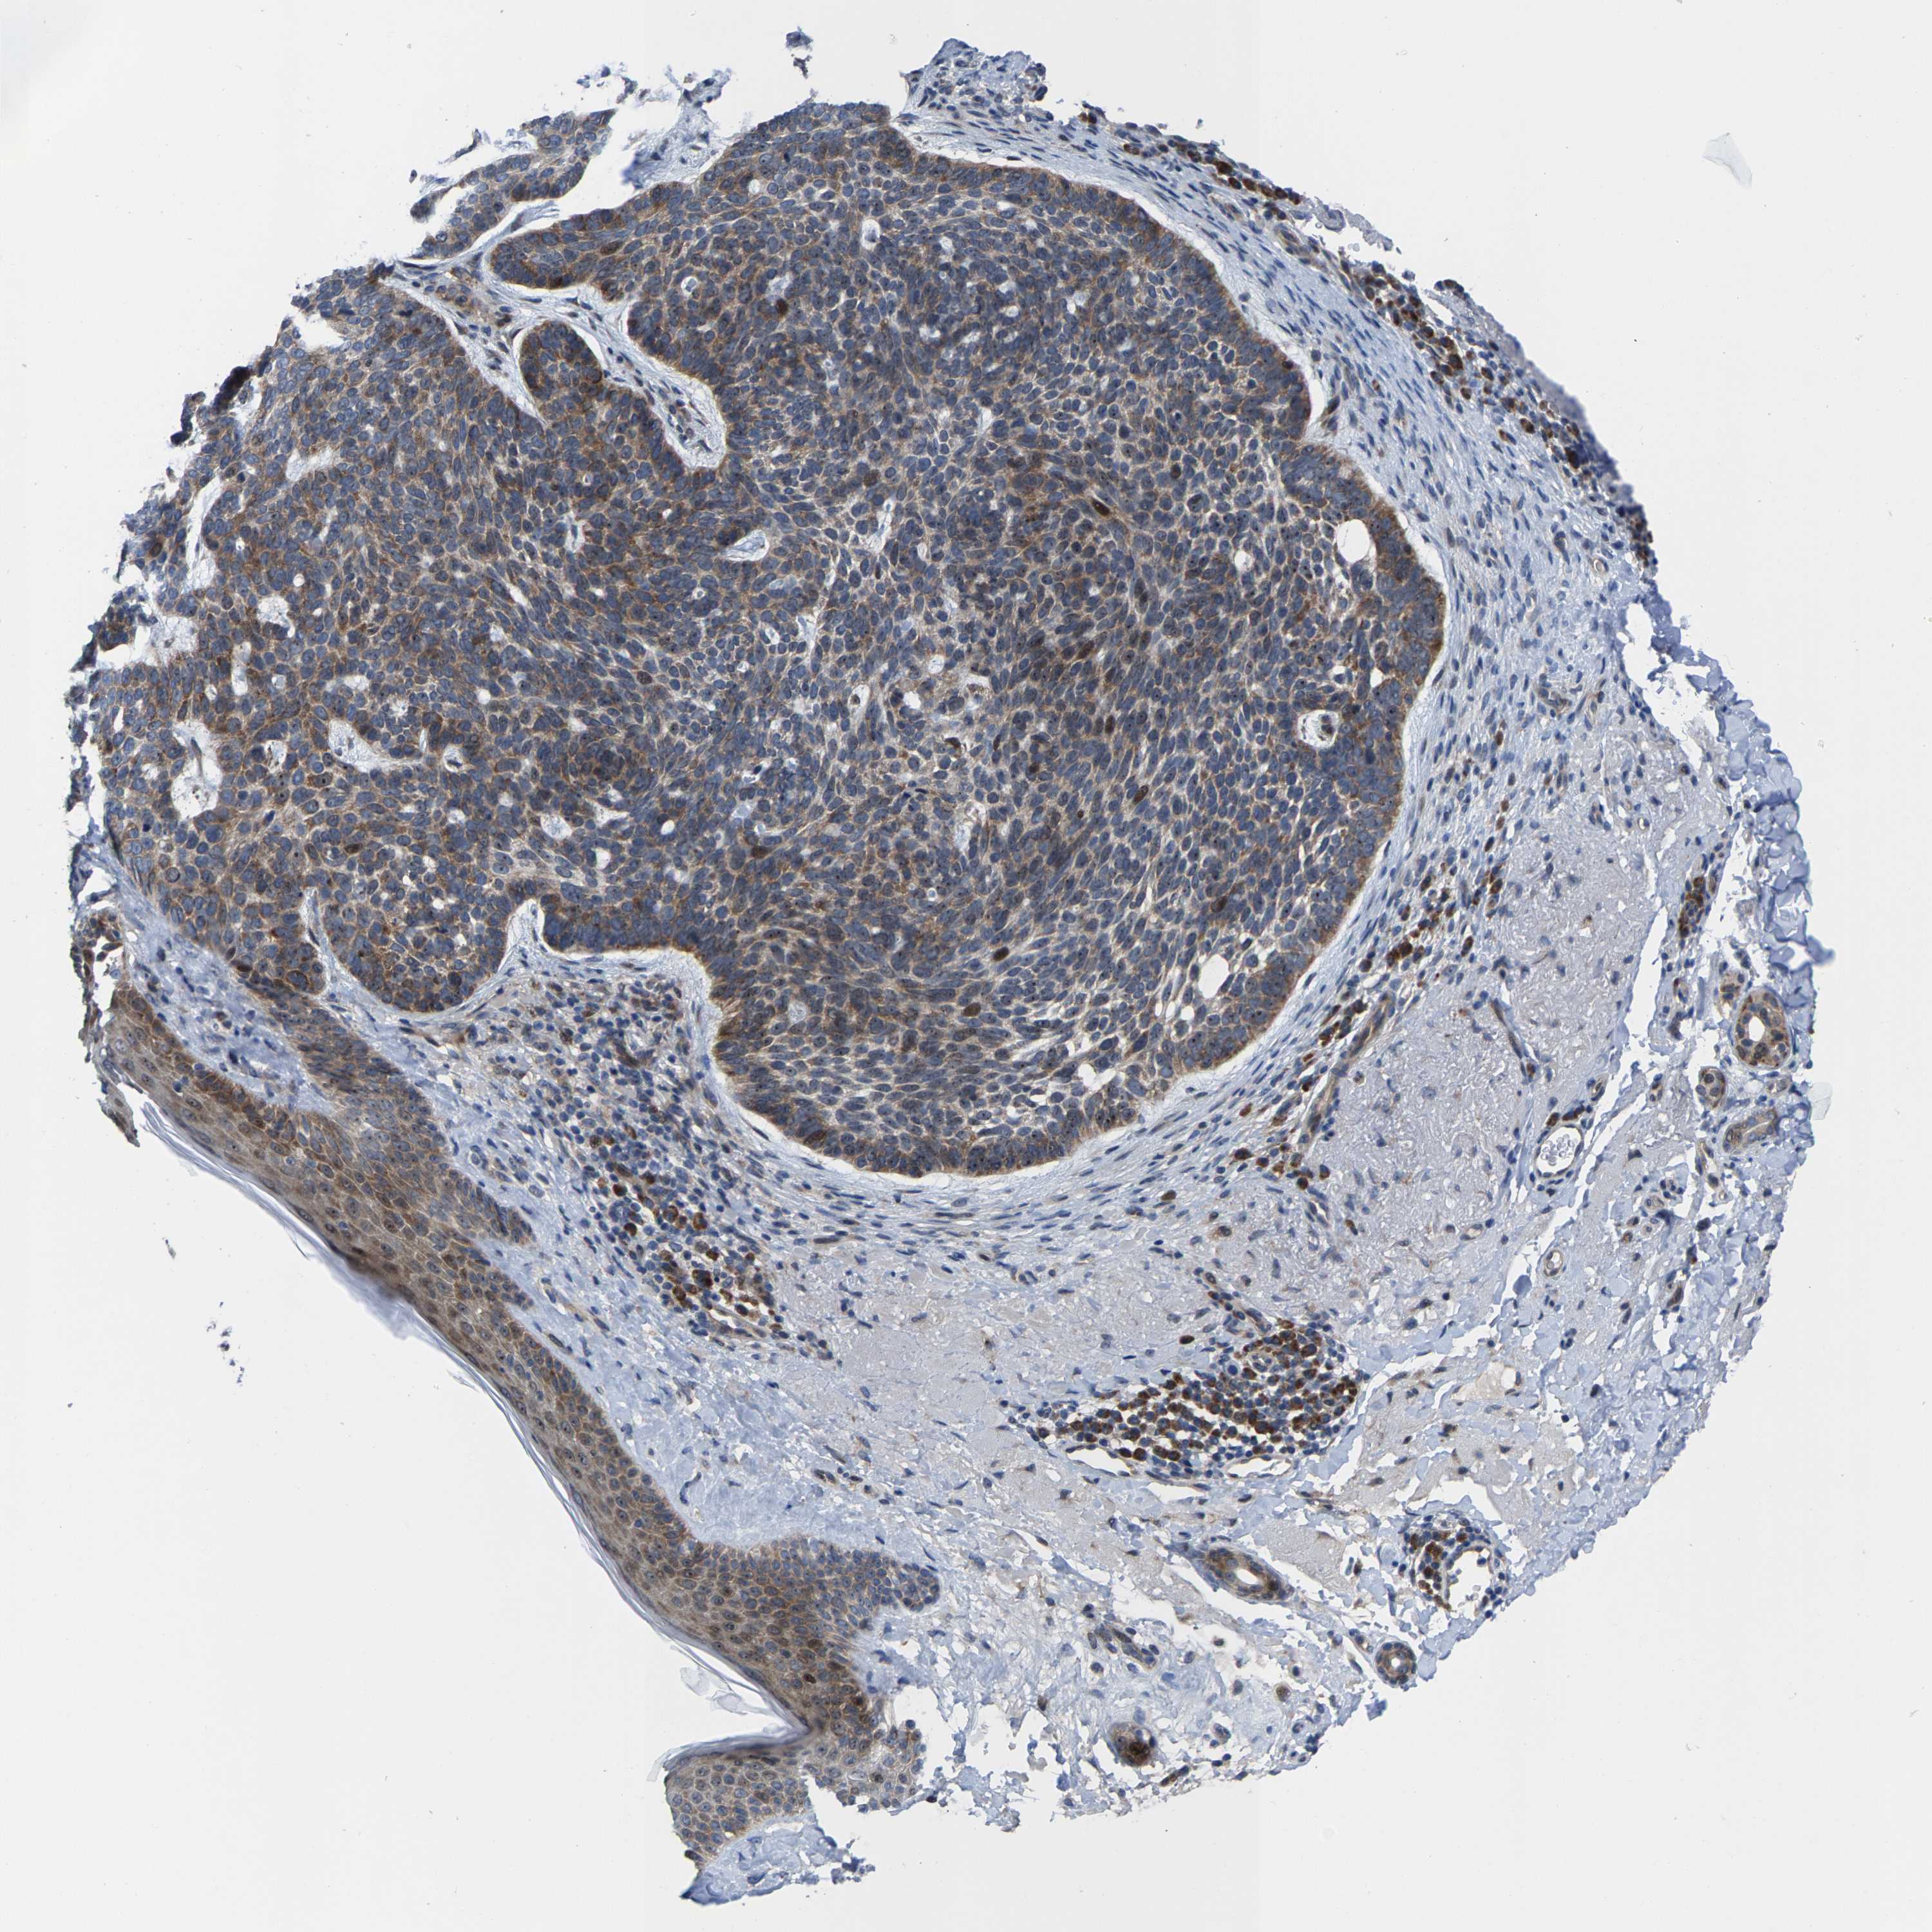

Basal cell and squamous cell cancer

SKIN CANCER - Protein expressioni

A mouse-over function shows sample information and annotation data. Click on an image to view it in a full screen mode. Samples can be filtered based on level of antibody staining by selecting one or several of the following categories: high, medium, low and not detected. The assay and annotation is described here.

Antibody stainingi

Antibody staining in the annotated cell types in the current human tissue is reported as not detected, low, medium, or high, based on conventional immunohistochemistry profiling in selected tissues. This score is based on the combination of the staining intensity and fraction of stained cells.

Each image is clickable and will lead to virtual microscopy that enables deeper exploration of all samples and also displays staining intensity scores, fraction scores and subcellular localization as well as patient and tissue information for each sample.

Antibody HPA020960

Antibody HPA020965

Staining

High

Medium

Low

Not detected

Intensity

Strong

Moderate

Weak

Negative

Quantity

>75%

75%-25%

<25%

None

Location

Nuclear

Cytoplasmic/membranous

Cytoplasmic/membranous,nuclear

Basal cell carcinoma

Squamous cell carcinoma, NOS

Squamous cell carcinoma, metastatic, NOS